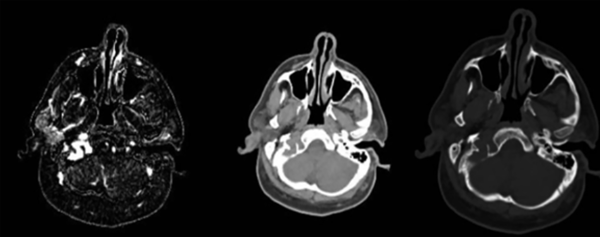

Figura 2. De izquierda a derecha: TC sin contraste que muestra una lesión isodensa localizada en la base del cráneo, en el centro: la ventana ósea de TC objetiva la presencia de erosión ósea a nivel del cóndilo occipital derecho, a la derecha la angiotomografía cerebral evidencia una lesión hipervascularizada localizada a nivel del canal del hipogloso.